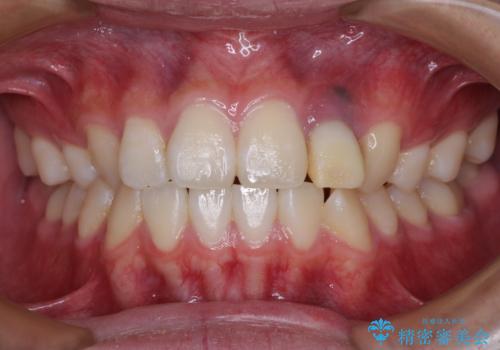

抜歯と言われた前歯 牽引してセラミッククラウンで保存する

- 他院で前歯の抜歯が必要と言われたとのことで来院された患者様です。

過去にぶつけたことで神経組織が壊死してしまったようで、その後むし歯が進行して歯肉深いところにまで進んでいる状態でした。

まずは部分矯正により歯を牽引し、歯肉や歯槽骨の位置を調整するために歯周外科処置を行い、治癒を待ってオールセラミッククラウンにて補綴治療を行うこととしました。

しっかりとむし歯を牽引したことで、クラウンの周りの腫れが引き、自然な口元に仕上げることができました。